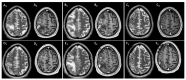

Central nervous system (CNS) lesions, especially invasive fungal diseases (IFDs), in immunocompromised patients pose a great challenge in diagnosis and treatment. We report the case of a 48-year-old man with acute myeloid leukaemia and probable pulmonary aspergillosis, who developed hyposthenia of the left upper limb, after achieving leukaemia remission and while on voriconazole. Magnetic resonance imaging (MRI) showed oedematous CNS lesions with a haemorrhagic component in the right hemisphere with lepto-meningitis. After 2 weeks of antibiotics and amphotericin-B, brain biopsy revealed chronic inflammation with abscess and necrosis, while cultures were negative. Clinical recovery was attained, he was discharged on isavuconazole and allogeneic transplant was postponed, introducing azacitidine as a maintenance therapy. After initial improvement, MRI worsened; brain biopsy was repeated, showing similar histology; and 16S metagenomics sequencing analysis was positive (Veilonella, Pseudomonas). Despite 1 month of meropenem, MRI did not improve. The computer tomography and PET scan excluded extra-cranial infectious-inflammatory sites, and auto-immune genesis (sarcoidosis, histiocytosis, CNS vasculitis) was deemed unlikely due to the histological findings and unilateral lesions. We hypothesised possible IFD with peri-lesion inflammation and methyl-prednisolone was successfully introduced. Steroid tapering is ongoing and isavuconazole discontinuation is planned with close follow-up. In conclusion, the management of CNS complications in immunocompromised patients needs an interdisciplinary approach.